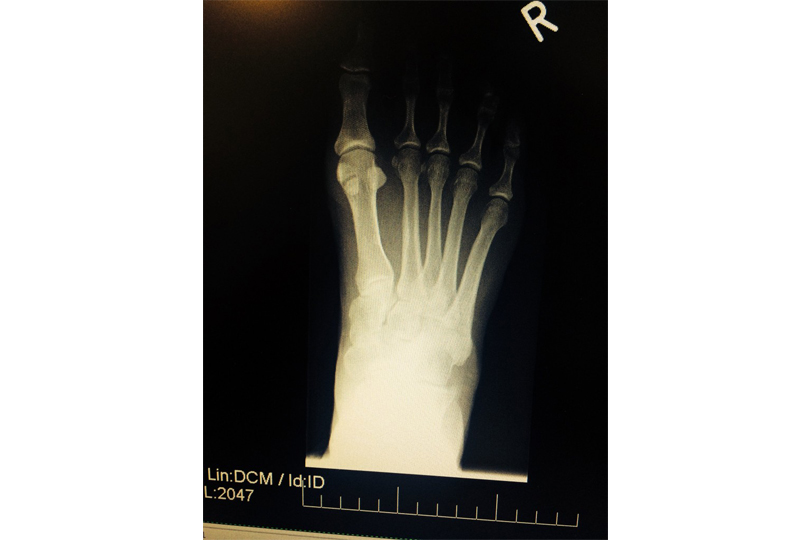

Bunion Surgery Treatment

Bunion Surgery is the only way to correct a bunion. Bunions usually get worse over time, so a bunion that is left untreated is likely to get bigger and become more painful. If your bunion is causing a significant amount of pain and is affecting your quality of life, your GP may refer you to […]